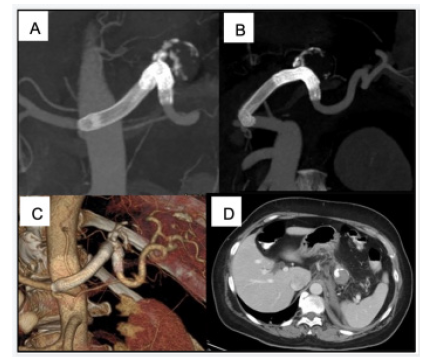

Complete exclusion of the aneurysm and patency of the splenic artery were confirmed at 6 months CT follow-up imaging (Figure 3). The patient became completely asymptomatic at follow-up.

Figure 3: CT angiography at 6-month follow-up: MIP (A) and 3D (B, C) reconstructions show complete exclusion of the aneurysm, patency of the splenic artery, and correct location of stent-grafts. Axial CT image (D) evidence normal splenic parenchyma in the venous phase, without signs of complications.